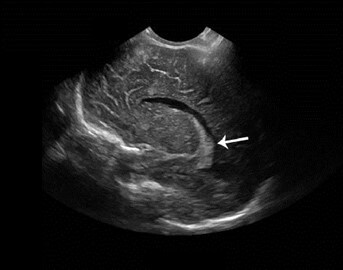

Neonatology Choroid Plexus Lobulation 2 Image